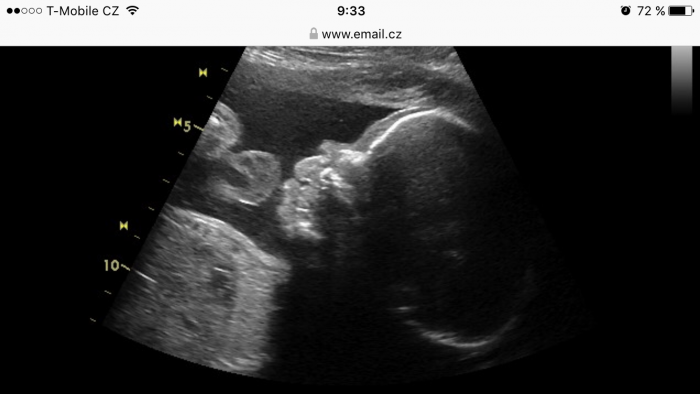

Bajuu, snad to das priste, ja teda taky malem vrhla :-/ dnes jsem si volala na výsledky a dobrý :) utz mi dela pokazde a cipek kontrolovala uz dvakrát, kdyz jsem ji rekla, ze me prtě tlaci, nebo poboliva bricho. 5.6. jdeme na 4D utz tak jsem zvedava a tesim se :) na posledním utz vypadal jak Homer Simpson, tak snad to byl jen nejaky odraz :-D přikládam foto :-D